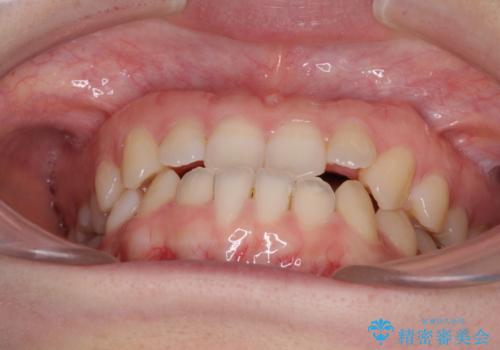

前歯のクロスバイト インビザラインによる矯正治療

- 前歯のクロスバイトとデコボコを気にして来院された患者様です。

骨格的に下顎前突傾向であるため、自己管理が煩わしくないようであれば、インビザラインによる矯正治療がお勧めとなります。

インビザラインを用い、下顎歯列を後方に移動させながら全市の被蓋を改善し、歯並びを整えていくこととしました。